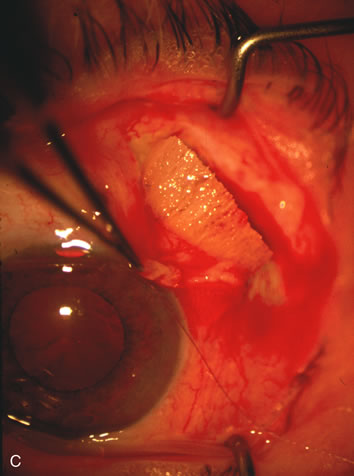

CASE 6: ANTICIPATED LENS EXTRACTION POST FAILED TRABECULECTOMY WITH ADVANCED DISC DAMAGE AND IOP OUTSIDE TARGET PRESSURE RANGE

The inflammation associated with lens extraction at any site usually causes complete failure of a marginal functioning bleb. In addition, pressure reduction by medical means is usually minimal in these recalcitrant cases, and combined surgery is indicated. In the past, these cases were approached with large-incision ECCE, clear corneal cataract incision, and bleb revision. Drawbacks included those mentioned earlier for large incision clear corneal cataract extraction, and bleb revision is often associated with conjunctival buttonholes, wound leaks, subconjunctival hematoma, destruction of friable sclera, and associated hypotony. With the advent of modern-day cataract surgery, a phacotrabeculectomy is often possible adjacent to the failed filter (Fig. 7). The ability to combine cataract extraction with implant and filtration surgery all through the same small incision has greatly improved outcomes for patients with marginal preoperative filters. There are several other viable options in this case. If the surgeon elects to remove the cataract through a temporal clear corneal incision, the bleb may be revised or a new adjacent filter fashioned. As mentioned earlier, revising a failed filter is technically challenging. If the surgeon believes it is not feasible to revise the filter or fashion a new one, a glaucoma drainage implant is a reasonable option combined with temporal lens extraction.172

Fig. 7. Phacotrabeculectomy adjacent to a failed filter in cataractous eye. The ability to combine small-incision cataract extraction with trabeculectomy all through the same incision adjacent to the failed filter allows the surgeon to work in a familiar superior area. Avoiding incisions into the existing bleb decreases conjunctival buttonholes, hypotony, operating room time, and subconjunctival bleeding. A. Appearance of failed bleb with exposure of superior temporal quadrant gained with a corneal traction suture. B. Prepare a limbus-based conjunctival flap and a scleral flap. C. This bleb is at high risk to fail again justifying the need for MMC, 0.2 mg/cc applied on a pledget for 4 minutes. D. Insert the keratome and perform phacotrabeculectomy in the usual fashion.